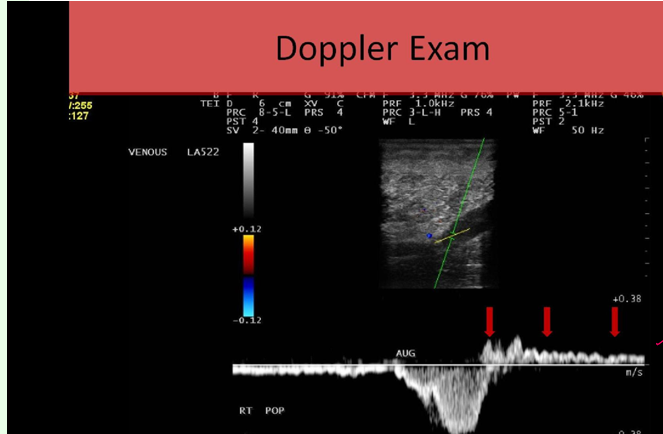

what does this show

abn distal augmentation due to reflux above baseline after augment

is this normal or abnormal

abnormal

retrograde flow → reflux